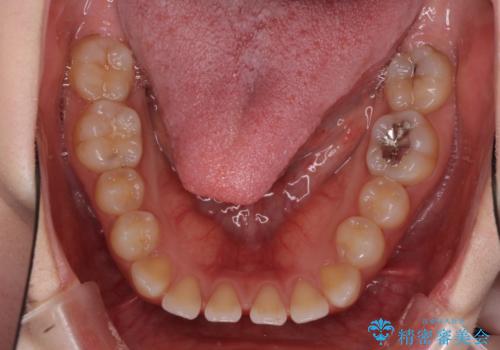

- 歯の欠損による隙間だらけの歯並びを気にして来院された患者様です。

上顎左右1本ずつ欠損していたため、歯列矯正により欠損部位にスペースを集め、その後欠損部位をインプラントにて補綴することとしました。

インビザラインによる矯正治療も提案しましたが、長時間の装着や自己管理が難しいとお考えで、ワイヤーによる矯正治療を行いました。

歯並びは比較的早めに整いましたが、インプラントを埋入するにあたって前後の歯根位置を改善する必要があり、矯正治療に期間を要することとなりました。